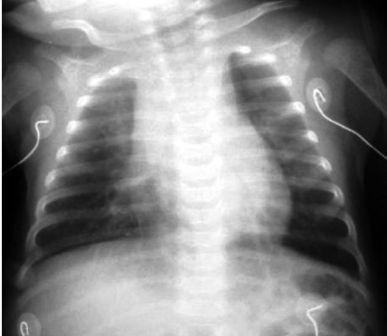

Paciente do sexo feminino, 4 anos e 8 meses, previamente hígida e eutrófica, sem vacinação prévia para vírus influenza. História de tosse e rinorreia há 2 semanas, com febre não aferida. Há 2 dias apresenta dor abdominal, vômitos e queda do estado geral. Admitida no pronto-socorro em mau estado geral, desidratada grave, normotensa, gemente, taquidispneica e taquicárdica. Temperatura: 38,1°C. Contagem de leucócitos: 10000/mm³, bastonetes 10/mm³, Frequência respiratoria: 36/min Tempo de enchimento capilar: 5 segundos.. Evoluiu com piora da taquidispneia, hipotensão, gemência, além de hepatomegalia, anasarca e presença de sopro cardíaco.

Exames laboratoriais evidenciaram anemia, acidose metabólica e elevação da concentração da proteína C-reativa. Eletrocardiograma evidenciou taquicardia sinusal (155 batimentos por minuto) e radiografia de tórax demonstrou aumento da área cardíaca, discreto derrame pleural à direita e infiltrado pulmonar difuso, sugestivo de congestão alveolar.

DISCUSSÂO: A reposição volêmica, de modo normal é de 20 ml/kg em 5-10 minutos. No entanto, cuidado com esse caso! Um coração aumentado na radiografia do tórax de uma criança com evidência de choque e débito cardíaco deficiente. Desse modo, neste caso não podemos administrar bolus de fluidos grandes ou rápidos. Preferencialmente, um bolus de fluido isotônico pequeno de 5 mL/kg a 10 mL/kg, com cautela e durante períodos relativamente mais longos (por exemplo, 10 a 20 minutos, em vez de 5 a 10 minutos) seria mais seguro. Os bolus grandes ou administrados muito rápido podem piorar a função cardíaca e aumentar o fluido já existente nos pulmões.